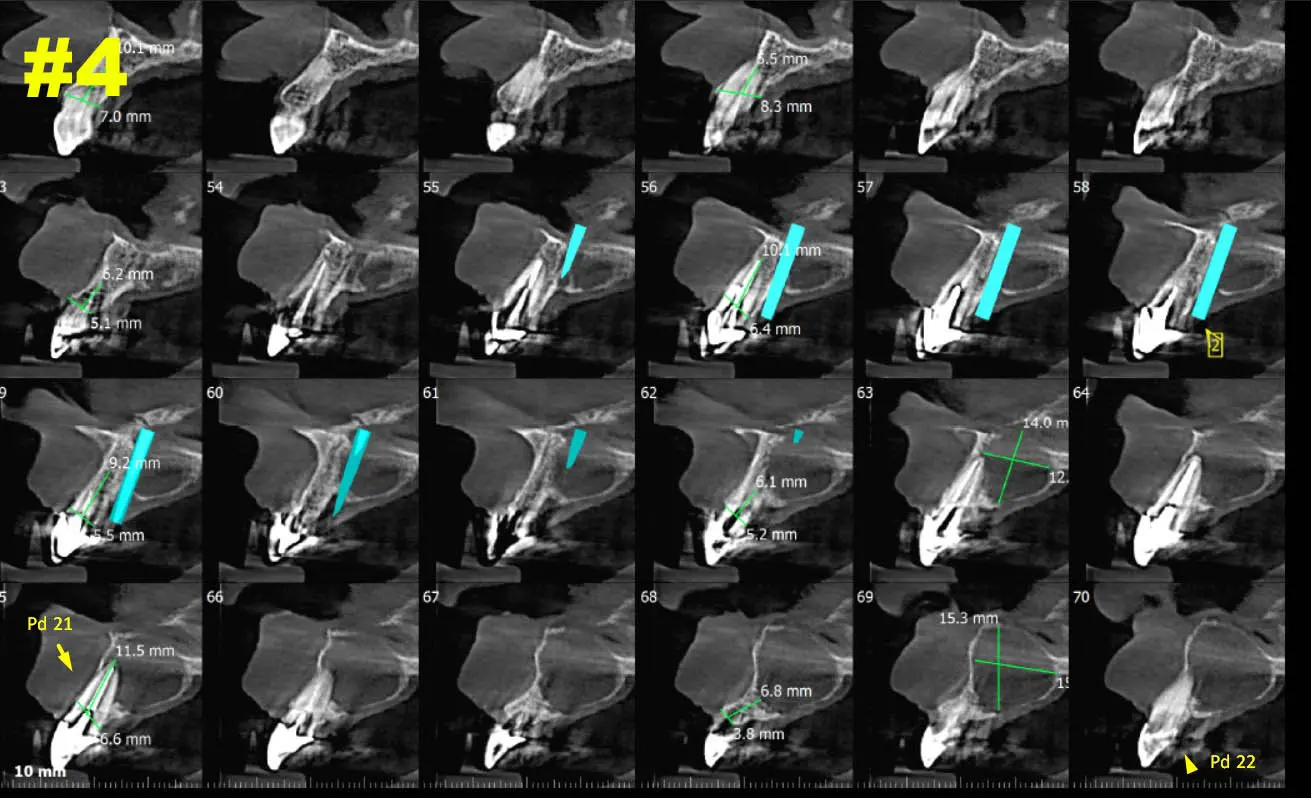

​Dicha lesión vemos que provoca expansión y abombamiento hacia piso de fosa nasal izquierda como también hacia cara palatina. Ver Imagen 2 Y 3. También se puede ver en una navegación  en cortes cada 1mm como se comporta la lesión - ver imágenes 4 y 5 (cortes transaxiales)